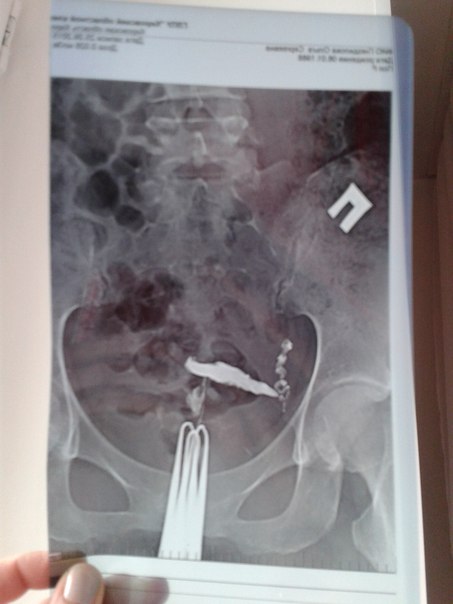

Всем планирующим привет! вот и прошла моя лапаро- и гистероскопия. боялась ооочень сильно, причем зря, перед этим сдавала МСГ, кто сдает МСГ (проверка труб при помощи введения контраста в полость матки и трубы, рентген), не верьте результатам, если они плохие!!! по результатам МГС: у меня была непроходима труба левая, матка чуть ли не плоской формы, в странном положении. вообщем лапароскопия всё опровергла! что в итоге... ТРУБЫ ПРОХОДИМЫ ОБЕ, МАТКА ПРАВИЛЬНОЙ ФОРМЫ, ОЧАГИ ЭНДОМЕТРИОЗА НА ФАЛЛОПИЕВЫХ ТРУБАХ(В ОБЛАСТИ ЯИЧНИКОВ), С ЛЕВОЙ И ПРАВОЙ СТОРОНАХ, А ТАК ЖЕ ОЧАГИ ЭНДОМЕТРИОЗА В МАТОЧНОЙ СВЯЗКЕ. Врач после операции со мной поговорила, сказала, что все очаги вскрыты и удалены. Сказала, можно беременеть пробовать уже в этом цикле, в течение года, если результата не будет, то на ЭКО! девочки, я так рада результатам, все проходимо, матка хорошая, без полипов, неужели причина кроется в этих очагах эндометриоза! я верю , что у нас всё получится! чуть более 2-ух лет планирования позади, гормоны, анализы, нервы и многое другое.....! дай Бог в этом или в ближайших следующих циклах в моём животике будет зарождаться новая жизнь, мой малыш!!!

вот так выглядела моя маточка и правая труба....